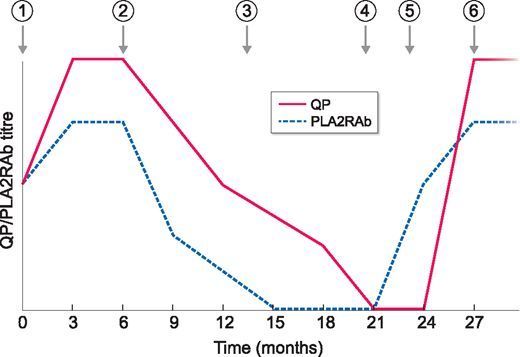

关于原发性膜性肾病PLA2RAb,不可不知的

关于原发性膜性肾病PLA2RAb,不可不知的